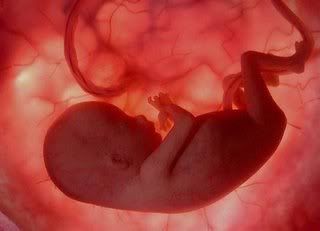

8 semaines de grossesse : où en est bébé ?

L'embryon mesure 3 cm et pèse 3 g. Dès la semaine 8 de votre grossesse, il commence à prendre figure humaine grâce aux traits qui s'harmonisent progressivement. Son nez et ses oreilles sont de plus en plus visibles et ses yeux et ses paupières continuent de se former. Le nerf optique est aujourd’hui constitué mais l'embryon ne peut pas encore voire.

Durant cette semaine 8 de grossesse, beaucoup de choses se passent au niveau du tronc : son cœur se cloisonne et son estomac, son pancréas et son foie font leur apparition. Même si ses organes génitaux se terminent, ils ne sont pas encore à leur place définitive, les glandes sexuelles ne sont donc pas encore visibles. Son système cardiaque et vasculaire est maintenant formé et on peut même entendre son petit cœur battre grâce au Doppler !

Votre embryon est devenu un fœtus et votre grossesse continue petit à petit.

7 semaines de grossesse : où en est bébé?

Durant cette semaine 7 de grossesse, l’embryon mesure 2.2 cm et pèse 2 g. Cette 7e semaine de grossesse est le début de l’ossification de son squelette. Son cou se développe et sa tête n’est plus directement posée sur le thorax. Pour le moment, on ne peut pas encore parler d’os mais de cartilage. Pour aider l’ossification, surveillez de près votre hygiène de vie et pensez à choisir les bons aliments.

Ses mains sont posées sur son ventre et ses jambes sont repliées, il commence à se redresser. Ses doigts et ses orteils se forment progressivement et sont de moins en moins palmés.

D’autre part, dès cette semaine 7 de grossesse, sa vision est en train de se mettre en place avec nerf optique, cornée, cristallin et rétine. Ses lèvres se dessinent peu à peu et les bourgeons dentaires se développent. Durant cette semaine 7 de grossesse, son estomac et ses intestins sont deux organes distincts et les deux lobes de son cerveau sont symétriques. Depuis la semaine passée, l’embryon bouge régulièrement mais vous ne le sentez pas encore.

6 semaines de grossesse : où en est bébé ?

Durant cette 6e semaine de grossesse, l’embryon mesure 1.7 cm et pèse 1.5 g, il a donc doublé sa taille en une semaine. Il est toujours replié sur lui-même et sa tête est penchée en avant. Sa tête est beaucoup plus grosse que le reste de son corps, son front est toujours bombé et son nez est aplati.

Dès cette 6e semaine de grossesse, sa bouche est épaisse et commence à se développer : les germes des dents de lait apparaissent et on discerne sa langue. Ses yeux immenses se sont rapprochés et sont recouverts d’une membrane qui deviendra par la suite ses paupières.

Durant la semaine 6 de grossesse, les membres de son corps s’allongent et on devine les articulations des coudes et des genoux. Quant à ses mains et ses pieds, ils ont des doigts palmés. Même si cela est encore imperceptible, Bébé bouge maintenant dans votre ventre. Toute la croissance de votre futur bébé se joue au cours du premier trimestre de votre grossesse.

5 semaines de grossesse : où en est bébé ?

Durant cette semaine 5 de grossesse, sa croissance continue. L’embryon mesure désormais entre 5 et 7 mm et son visage commence à prendre forme progressivement. Dès la cinquième semaine de grossesse, les yeux forment une petite saillie, le nez et la bouche se creusent et les oreilles ne sont encore que des petites fentes.

Celui qui ressemblait encore la semaine passée à une virgule perd aujourd'hui sa queue tandis que sa tête reste toujours penchée vers l’avant. Ses bras et ses jambes commencent à se développer dès cette semaine 5 de grossesse.

Depuis une quinzaine de jours, son cœur bat mais aujourd’hui, il a presque doublé de volume. De plus, dès cette semaine 5 de grossesse, il bat deux fois plus vite que celui d’un adulte. D’autre part, le système nerveux poursuit son développement et les principaux organes de votre fœtus, à savoir les poumons, l’estomac, les reins, les organes sexuels et le foie, se sont presque complètement formés. Pour le bien-être de votre Bébé, continuez donc de faire très attention à votre hygiène de vie dès cette semaine 5 de grossesse.

Côté bébé

L’embryon mesure entre 2 et 4 millimètres. Son poids est encore négligeable.

Son développement à 4 semaines de grossesse :

De crevette, l’embryon devient hippocampe : il s’allonge encore. Sa tête devient plus proéminente et il semble réellement posséder une queue. Pour l’instant, il n’a pas d’excroissance pour les jambes. On remarque également des pulsations, c’est le premier « rythme cardiaque » ! Bien sûr, le cœur de l’embryon n’est pas encore vraiment formé. Il possède seulement deux chambres (au lieu de quatre, à terme).

A ce stade, le système le plus avancé est le système nerveux central : le tube neural est désormais formé et, à son extrémité, le cerveau est en formation (c’est pour cela que la tête semble si grosse). Le foie va commencer à apparaître, avant le reste du système digestif. A ce stade, l’embryon est nourri par le corps jaune (résidu de l’ovulation) en attendant que le placenta soit formé.

L’œuf s’est allongé mais reste minuscule. Votre bébé mesure en effet moins de 2 millimètres.

Son développement à 3 semaines de grossesse :

Le fœtus ressemble à une petite crevette de la taille d’un grain de riz. Néanmoins, on distingue déjà une tête et une queue. Sur l’arrière, on voit une ligne, première ébauche du tube neural qui deviendra le cerveau et la moelle épinière. Le placenta et le cordon ombilical poursuivent eux aussi leur croissance, même s’ils sont encore loin d’atteindre leur pleine maturité.